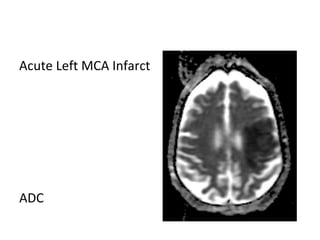

Acute Left MCA Infarct

T1

T2

DWI

ADC